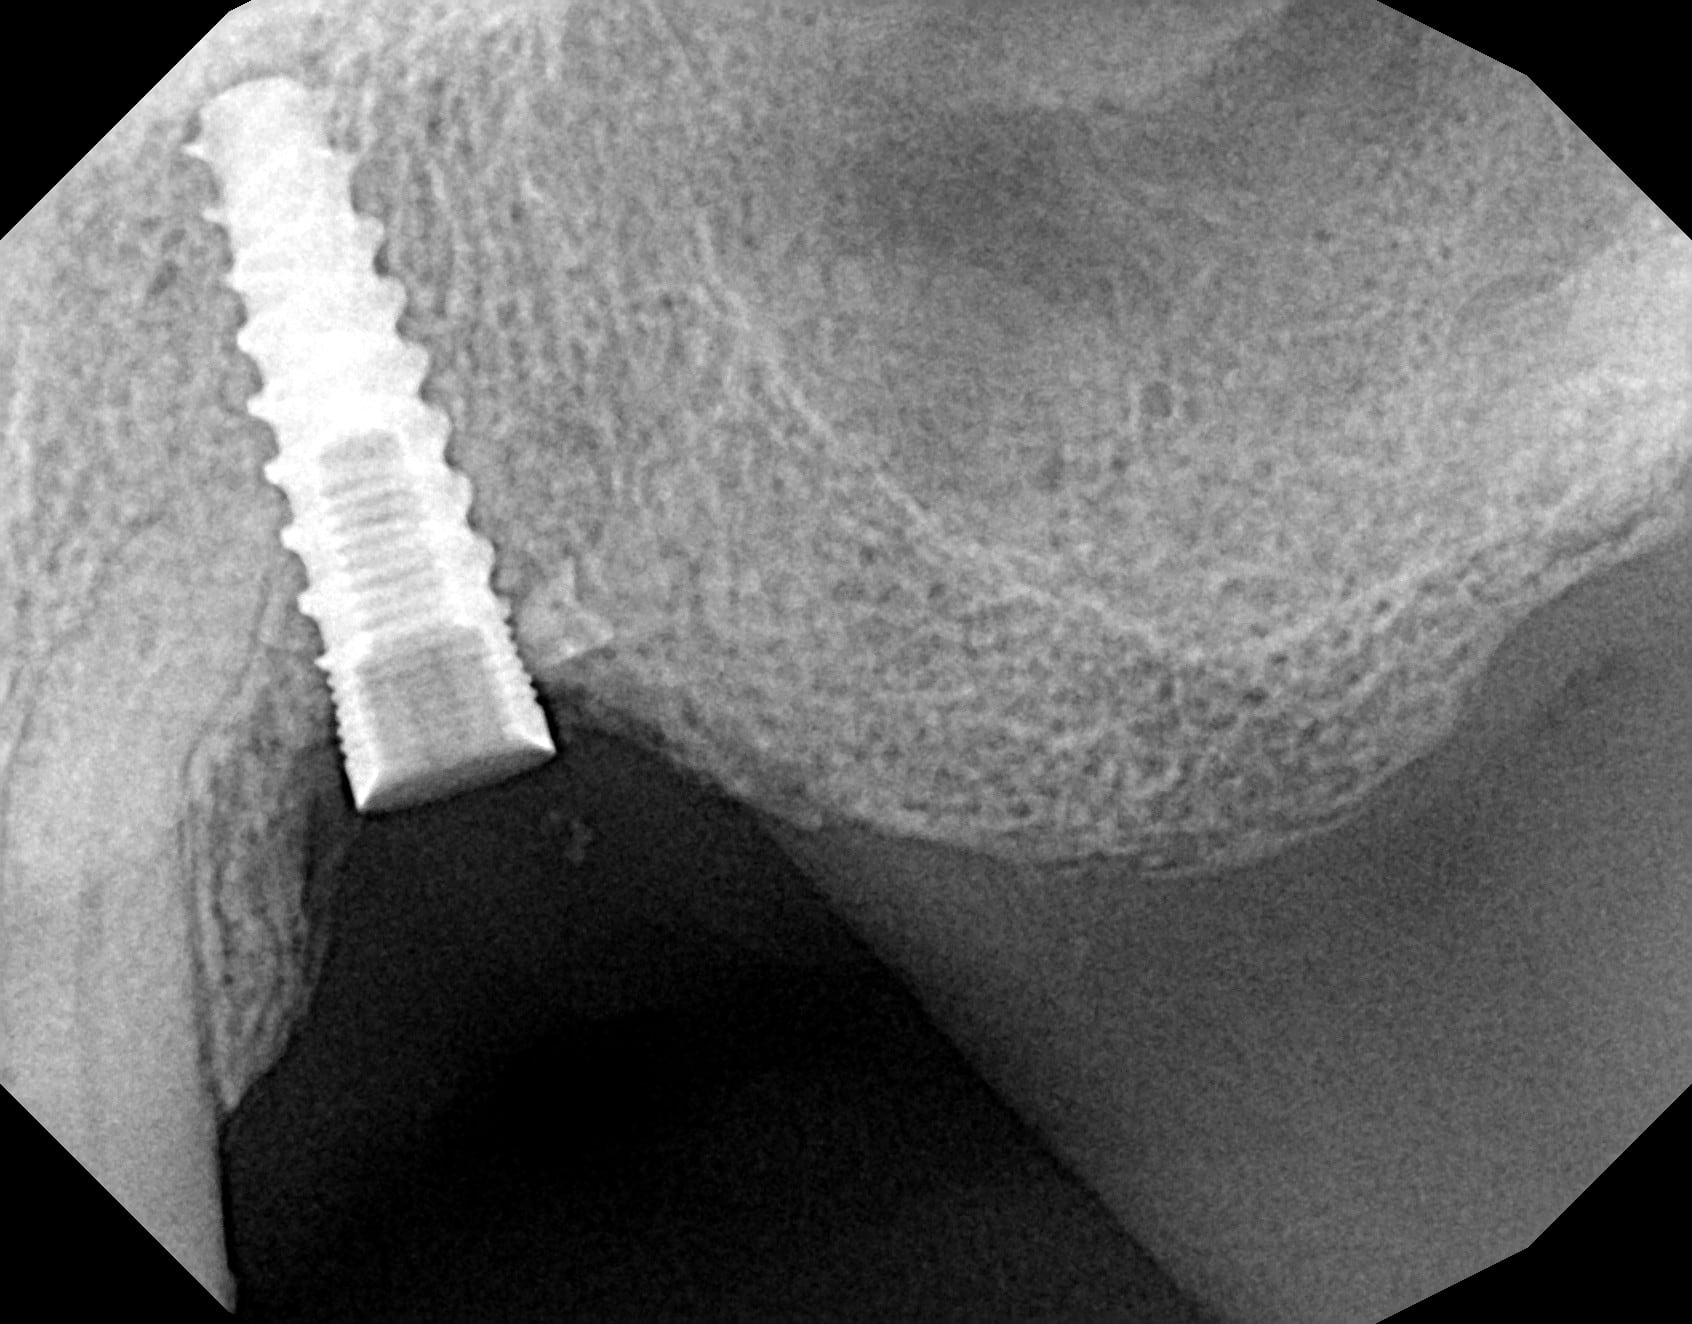

Quelqu'un à une idée sur la marque de cet implant (pilier dévissé pendant son hospitalisation)

plus de 10 ans, mais le patient ne se souvient pas exactement.

MIS seven

https://www.spotimplant.com/fr/implants-dentaire/mis/seven-2